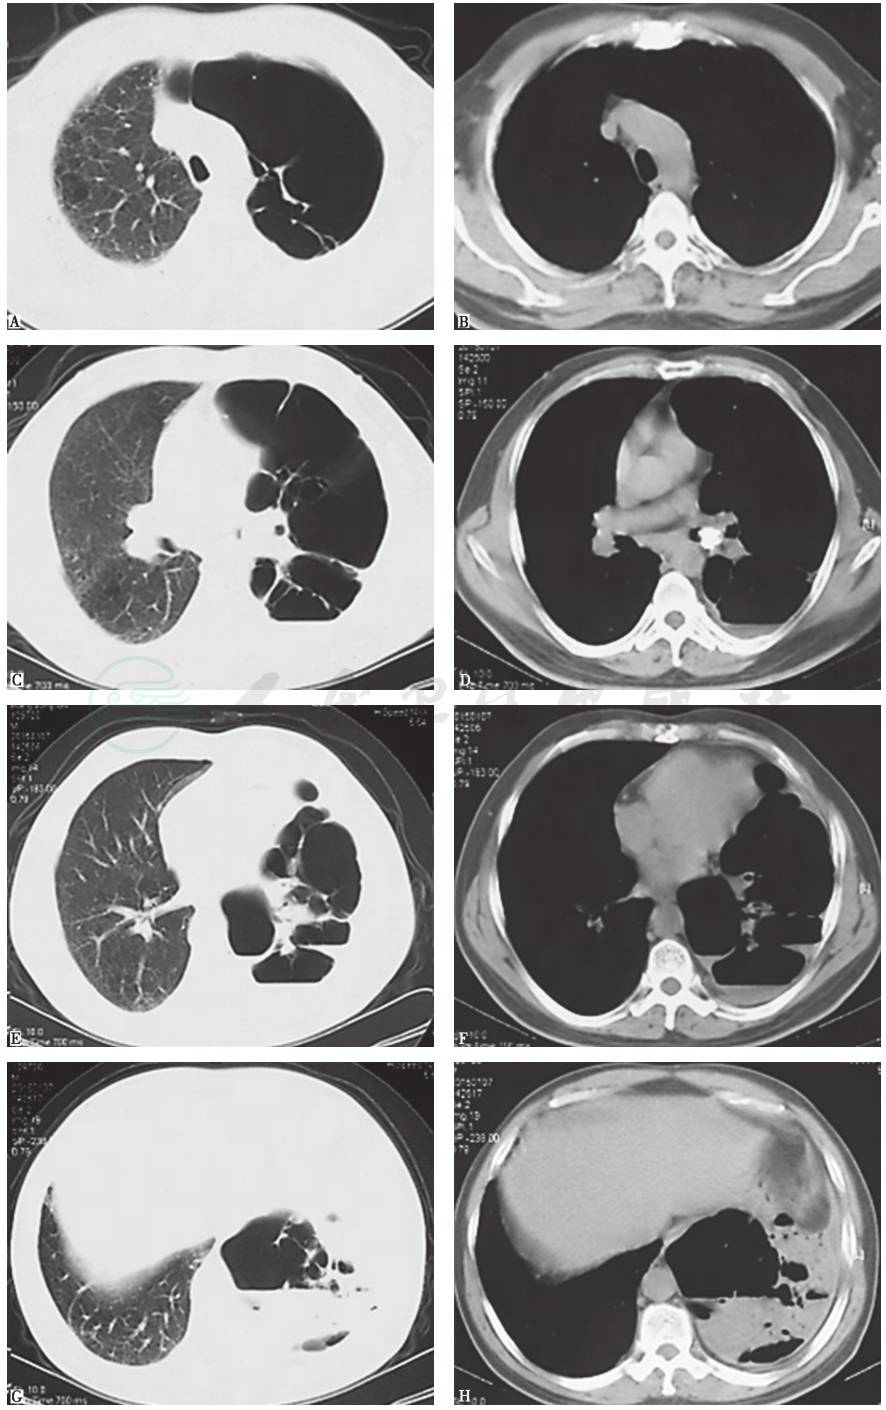

近13年来,患者胸部X线和CT均表现为左肺从初始体积大致正常,逐渐出现左肺体积减小,肺实质高密度影肺炎样改变;随着病情发展出现多发肺大疱、肺脓肿和肺毁损(图3~图10),并见左主支气管内病灶逐渐增大,最终导致管腔闭塞。

图4 10年半前胸部CT表现

胸部CT可见左主支气管被高密度钙化灶不全阻塞,左肺体积缩小,但透过度略有增高,同时伴左侧胸膜弥漫性增厚

引自:主编:.呼吸系统疑难病例诊疗辨析.第1版.ISBN:978-7-117-26415-0

图7 6年半前胸部CT表现

胸部CT可见左主支气管被高密度钙化灶阻塞进一步加重,但左上肺体积增大含气增多,左下肺略缩小伴局限性斑片状高密度病灶和膨胀不全;右肺代偿性含气增多;左侧胸膜弥漫性病变减轻

图8 4年半前胸部CT表现

胸部CT可见左主支气管被高密度钙化灶阻塞进一步加重,管腔几近完全阻塞,左肺体积略缩小伴局限性不张,左上肺代偿性肺气肿和肺大疱进一步加重;右肺代偿性含气增多;未见左侧胸膜病变